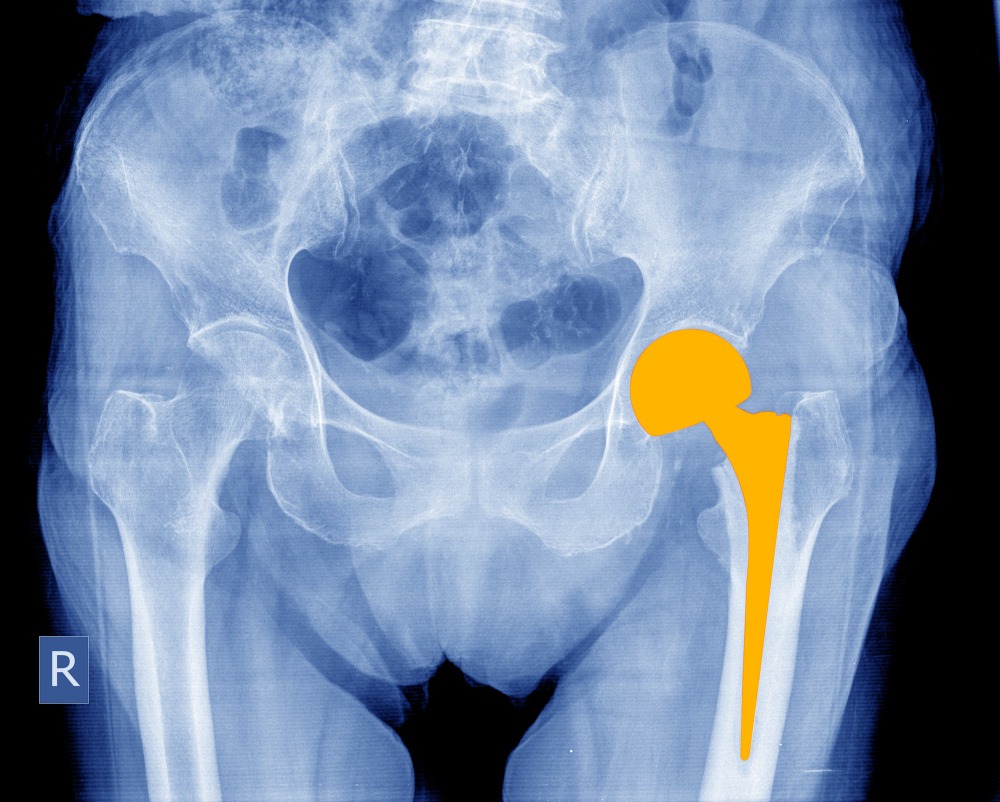

Partial Hip Replacement in Colaba for Focused Joint Relief

Hip pain isolated to one part of the joint often goes unnoticed until it starts disturbing daily habits. Many individuals in Colaba hesitate to seek help, thinking the only option is a full replacement. Speaking with Dr. Sujit Korday helps them understand how partial hip replacement can target the damaged section without unnecessary intervention.

This approach preserves healthy bone and tissue, allowing more natural joint movement and a smoother recovery experience. People value how it offers relief without the extent of a total replacement, making it ideal for selected cases. Understanding the benefits helps reduce confusion for those unsure about the difference between partial and complete replacement.